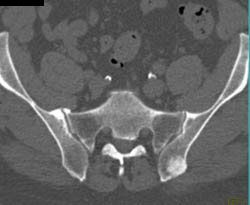

Plasmacytoma